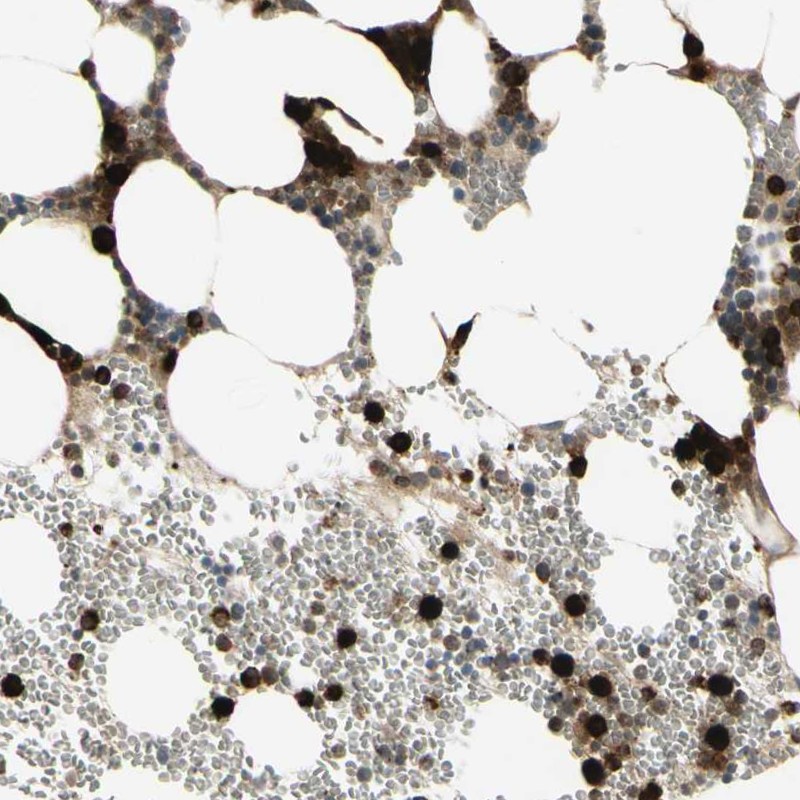

Immunohistochemistry analysis in human bone marrow and cerebral cortex tissues using Anti-CCNB2 antibody. Corresponding CCNB2 RNA-seq data are presented for the same tissues.